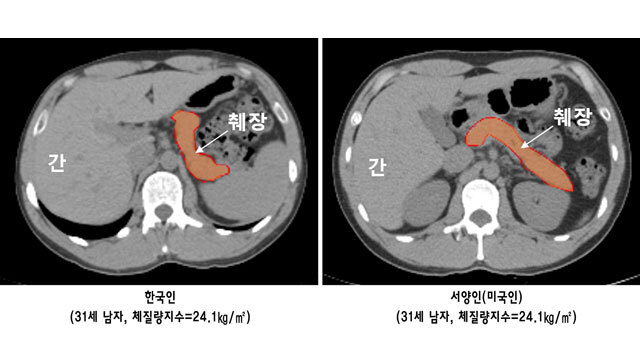

분당서울대병원 임수 교수팀은 체격이 유사한 30대 한국인과 서양인 43쌍을 최첨단 컴퓨터 CT로

췌장의 부피를 측정해 1대1로 비교·분석했습니다. 그 결과, 서양인에 비해 한국인의 췌장 크기는 12.3% 작고,

췌장 내 지방 함량은 22.8% 더 많은 것으로 나타났습니다.